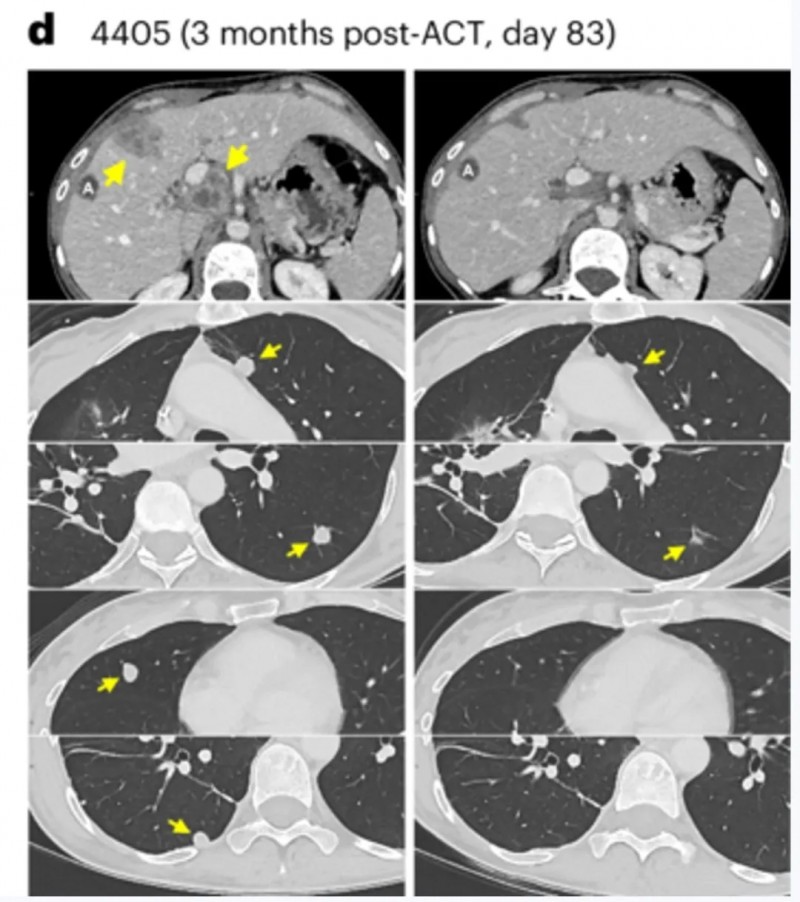

患者4405(转移性直肠癌)在TCR-T细胞回输后,影像学检查证实其肝转移、门静脉淋巴结及多发肺转移病灶均完全消退。

▲图源“Net Med”,版权归原作者所有,如无意中侵犯了知识产权,请联系我们删除